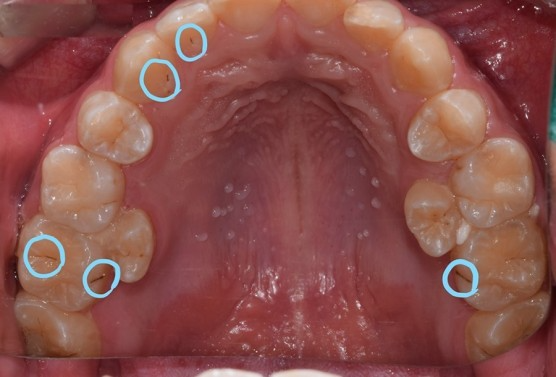

고등학생 남자아이의 입안입니다. 치아에 까만 점들이 보이죠?

정지우식이 될 가능성이 높은 충치

4개의 치아가 충치가 있긴하죠.

하지만 정지우식이 될 가능성이 높아 치료는 하지않고, 경과 관찰을 더하면 될 듯 합니다.

실제로 2년동안 충치는 그대로 잘 유지 되고 있습니다.

양쪽 충치의 모습이 보입니다.

파란색 치아는 치료를 하지않고 경과관찰을 하기로 한 충치이고

빨간색 치아는 치료를 진행한 충치입니다.

차이가 느껴지시나요?

파란색 치아도 관리가 잘되지 않는다면 빨간색 치아처럼 충치가 진행될 수 있습니다.

하지만 관리가 잘된다면 정지우식이 되고 치료할 필요가 없겠죠.